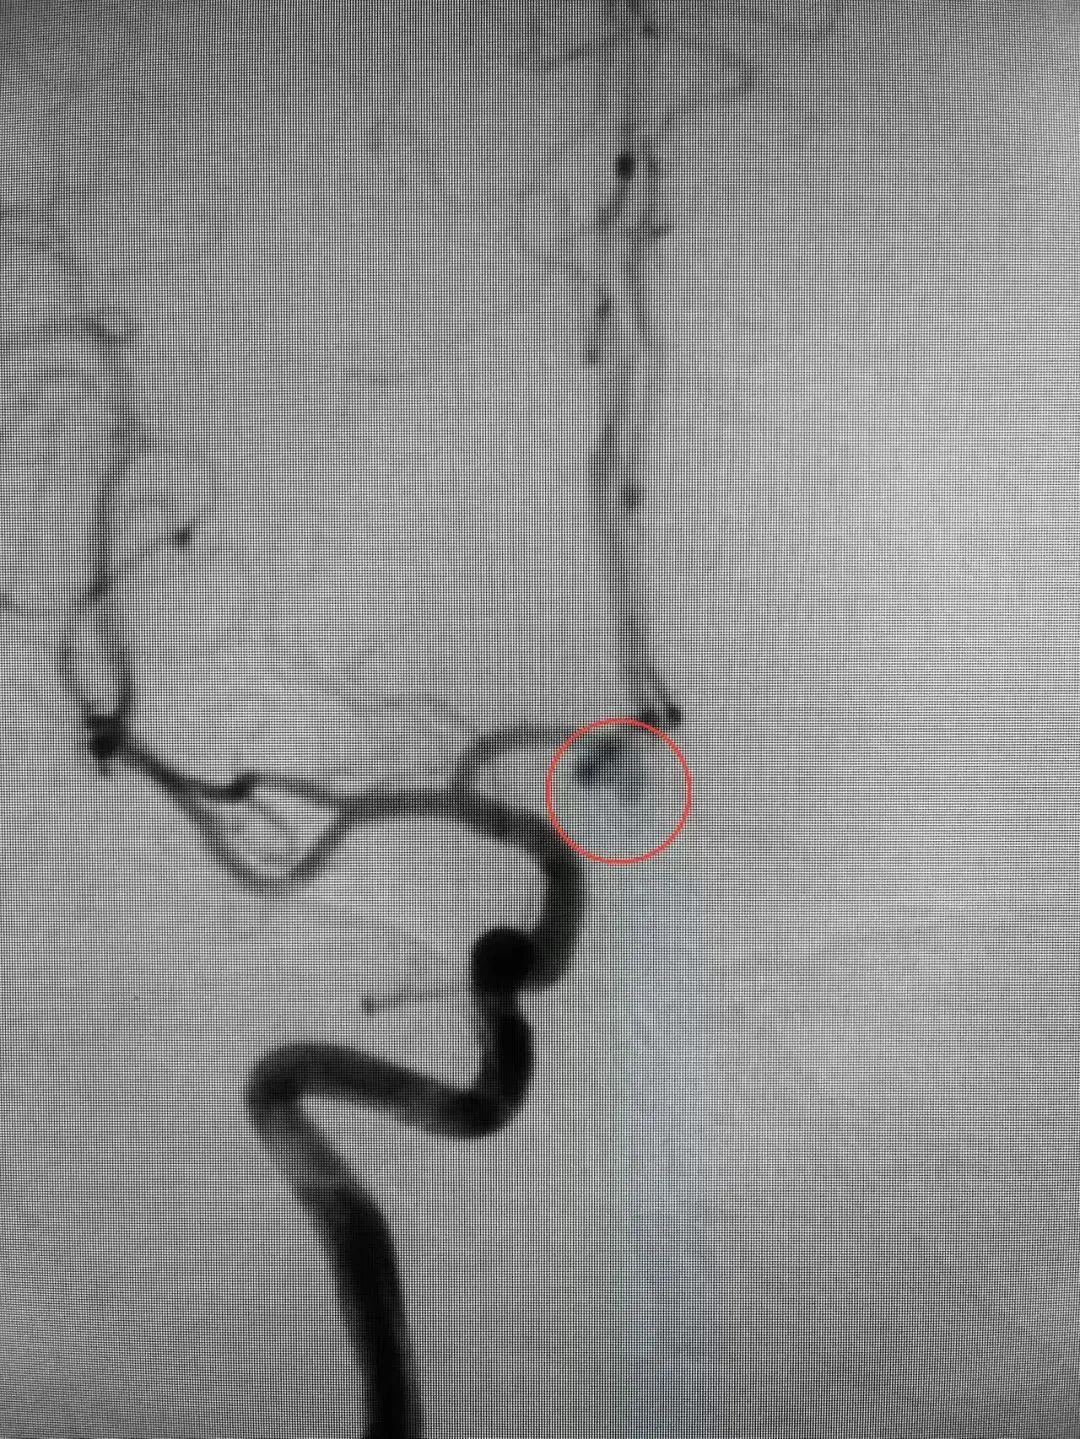

近日,殷女士在家中突发头痛,随后意识丧失,被家人送至幸运轮盘娱乐中心 急诊科。医生迅速安排颅脑CT扫描等相关检查。结果显示蛛网膜下腔出血,CTA显示前交通动脉瘤。情况紧急,幸运轮盘娱乐中心 脑病科过智伟医生考虑殷女士此次发病与动脉瘤破裂有关,前交通动脉瘤破裂死亡率高达30-40%,死亡风险高,需立即手术处理。在与殷女士家属进行充分沟通,详细解释了病情和治疗方案后,医护团队立即实施了急诊局麻下全脑血管造影+全麻颅内动脉瘤栓塞术。手术造影过程中,发现造影剂外渗,动脉瘤仍在持续出血,死亡率随之提高。医护团队沉着冷静,最终成功排除了殷女士脑中的这颗“不定时炸弹”。

△术前△ △术后△